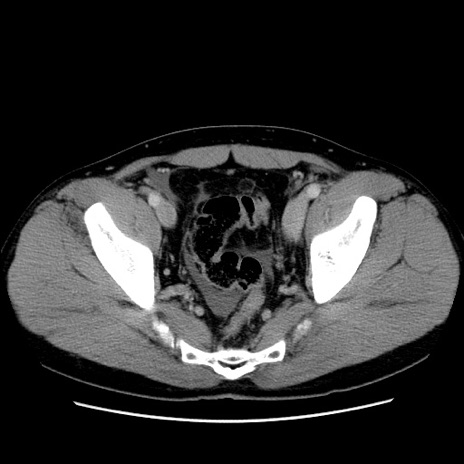

症例4(横断像)

【症例】30歳代男性

【主訴】腹痛、嘔吐

【現病歴】昨晩から突然の腹痛あり、その後嘔吐、軟便も出現。腹痛が改善しないため救急搬送となる。2日前にしめ鯖の食事歴あり。

【身体所見】意識清明、苦悶様、BP 135/90mmHg、BT 35.7℃、腹部:平坦、やや硬、心窩部〜臍部に自発痛、圧痛あり、筋性防御+、反跳痛-

【データ】WBC 8100、CRP 0.57